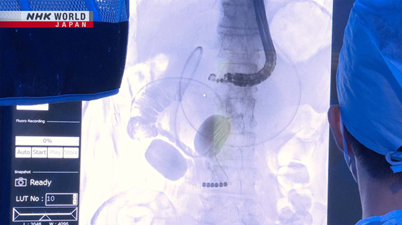

- New Approach To Treating Pancreatic Disease

- 膵臓疾患治療への新たなアプローチ、医療の最前線

テーマは「膵臓疾患治療への新たなアプローチ」体の奥で進行する膵臓疾患に挑む、

超音波内視鏡による早期発見や新たな治療法の最前線を紹介します。 - 【番組サイト】